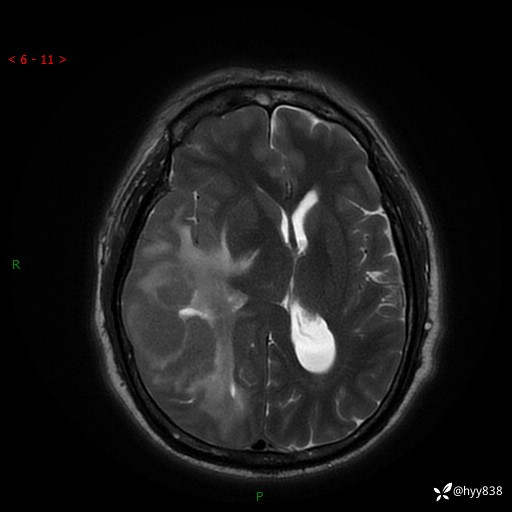

患者性别:男

患者年龄:56岁

简要病史:外院CT提示脑膜瘤,为进一步诊治来我院

辅助检查:MRI

临床诊断:颅脑占位

颅脑MRI平扫+增强

脑膜瘤 (78)

脑膜孤立性纤维性肿瘤/血管外皮瘤 (1)

单发性纤维性肿瘤 (39)